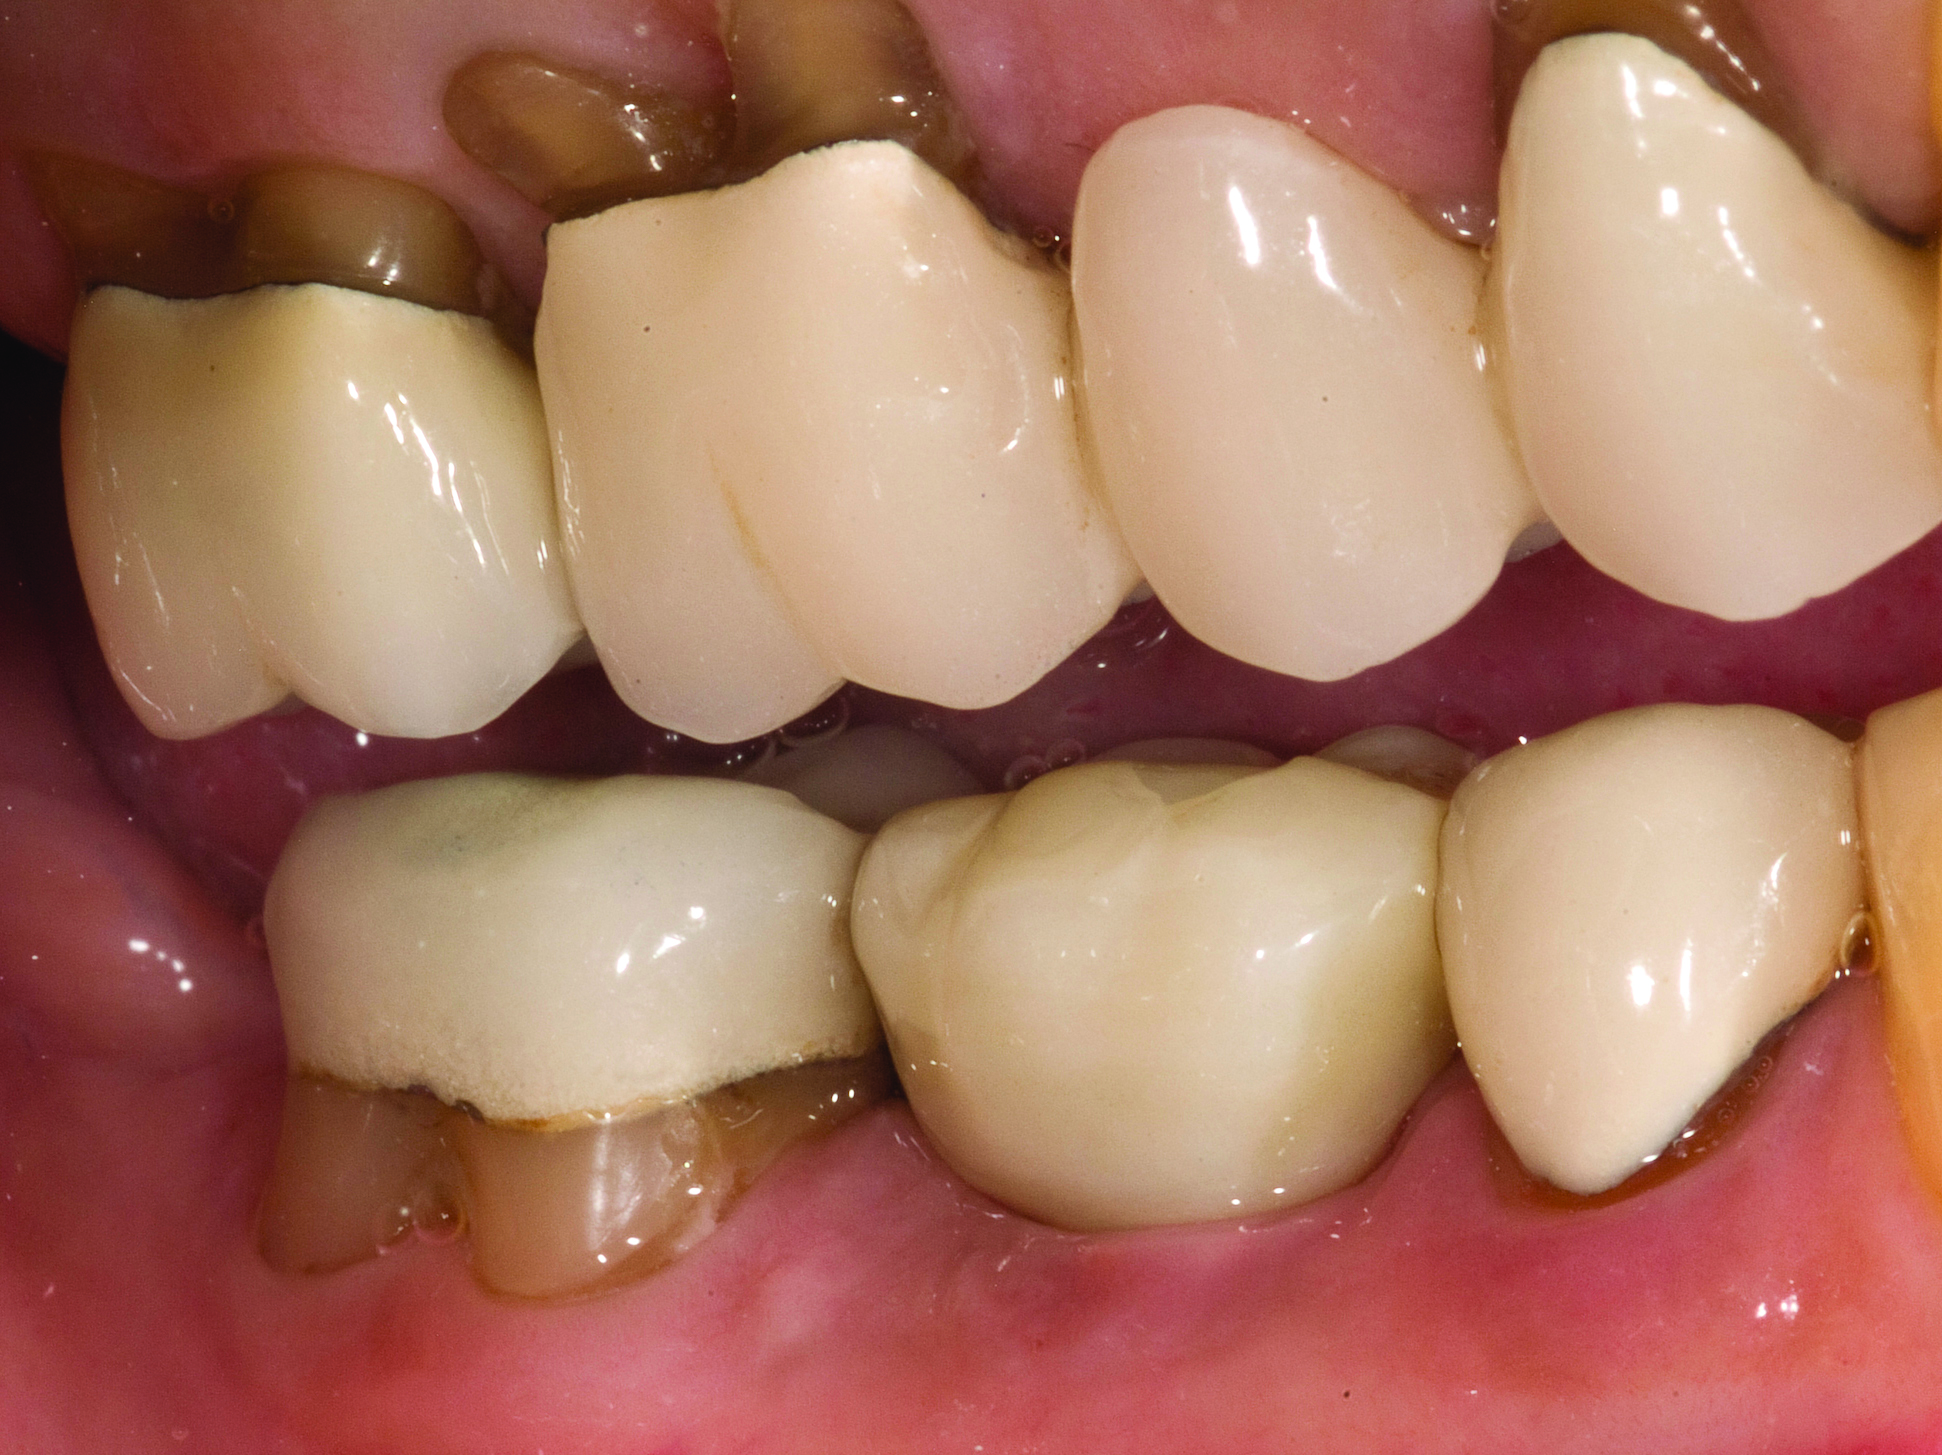

A mandibular right first molar was extracted due to an advanced Class III furcation and an irreversible pulpitis—a combination lesion. An immediate implant placement protocol was elected, and a PEEK abutment was placed on the implant (Figure 1). After 3 months of healing, a scan body was placed on the osseointegrated implant (Figure 2 and Figure 3), and an intraoral scan was taken (TRIOS Pod) (Figure 4) for the fabrication of a screw-retained crown.

Fig 1. Immediate implant placement with a PEEK healing abutment to contour soft tissue, mandibular right first molar.

Figure 1